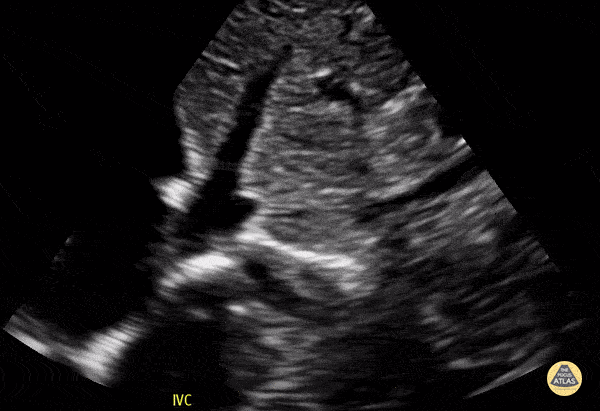

Normal IVC in a 4-year-old preschooler. Contributor: Jaron Smith, MD, Phoenix Children's Hospital

View: Unspecified Parasternal Long Axis Parasternal Short Axis Apical Four-Chamber Subcostal Four-Chamber Subcostal Inferior Vena Cava Right Upper Quadrant Left Upper Quadrant Suprapubic Longitudinal Suprapubic Transverse Subxiphoid Anterior Thoracic Phrenic